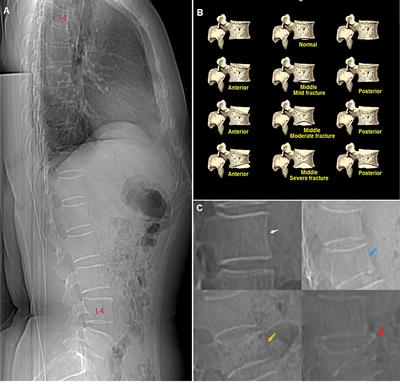

Comparison of four tools to identify painful new osteoporotic vertebral fractures in the postmenopausal population in Beijing